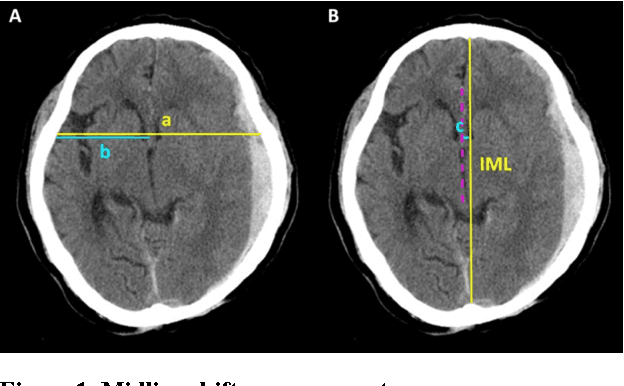

Abstract:Brain CT has become a standard imaging tool for emergent evaluation of brain condition, and measurement of midline shift (MLS) is one of the most important features to address for brain CT assessment. We present a simple method to estimate MLS and propose a new alternative parameter to MLS: the ratio of MLS over the maximal width of intracranial region (MLS/ICWMAX). Three neurosurgeons and our automated system were asked to measure MLS and MLS/ICWMAX in the same sets of axial CT images obtained from 41 patients admitted to ICU under neurosurgical service. A weighted midline (WML) was plotted based on individual pixel intensities, with higher weighted given to the darker portions. The MLS could then be measured as the distance between the WML and ideal midline (IML) near the foramen of Monro. The average processing time to output an automatic MLS measurement was around 10 seconds. Our automated system achieved an overall accuracy of 90.24% when the CT images were calibrated automatically, and performed better when the calibrations of head rotation were done manually (accuracy: 92.68%). MLS/ICWMAX and MLS both gave results in same confusion matrices and produced similar ROC curve results. We demonstrated a simple, fast and accurate automated system of MLS measurement and introduced a new parameter (MLS/ICWMAX) as a good alternative to MLS in terms of estimating the degree of brain deformation, especially when non-DICOM images (e.g. JPEG) are more easily accessed.